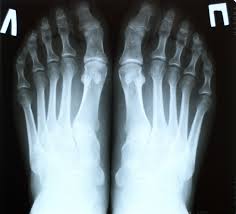

Инструментальные исследования болезни

Такой вид диагностики назначается каждому пациенту, когда есть подозрение на подагру. Необходимо выделить обязательные методы обследования:

- Ультразвуковая диагностика зоны суставов;

- Компьютерная томография;

- Рентген болевого участка;

- Сцинтиграфия.

На УЗИ пациента можно обнаружить болезнь только в стадии обострения. В первые 3 дня приступа картина сразу понятна для опытного врача. Через неделю после болей подагра уже не заметна при диагностике.

На последней стадии болезни УЗИ позволит увидеть, какие суставы начинают деформироваться. Процедура поможет определить глубокие тофусы и их размеры.

Благодаря компьютерной томографии можно получить точные снимки с пораженного участка тела. Исследование покажет степень заболевания, состояние суставов и место расположения тофусов. Если подагра на ранней стадии, тогда на снимке будет небольшое уплотнение на тканях.

Рентгеновское исследование подагры

Чтобы получить точную картину заболевания и отличить подагру от артрита, врач назначает рентген больного сустава. В момент тяжелой стадии на снимках сразу видна болезнь. На мягких тканях показано небольшое уплотнение и затемненные части. При диагностике костей и суставов врач увидит состояние поверхности и основные признаки заболевания. Если на снимке есть темные участки на фоне светлых тканей, это говорит о наличии подагры в организме.